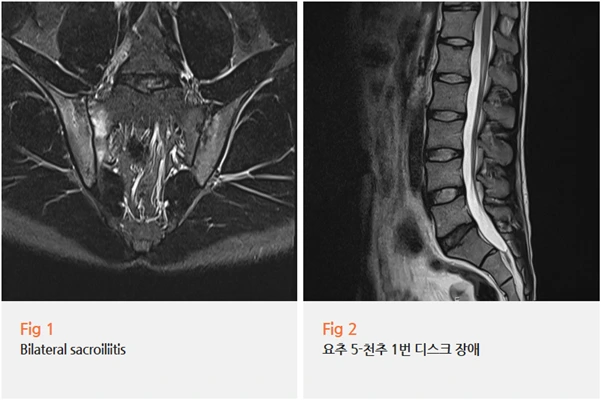

정확한 원인을 파악하기 위해 당일 요추부 MRI와 천장관절 MRI를 함께 시행했어요.

결과는 두 가지였습니다.

요추 5번-천추 1번 사이 추간판 팽윤, 그리고 양측 천장관절염.

추간판 팽윤, 즉 디스크가 약간 膨出되어 있는 건 어느 정도 예측했지만,

양쪽 천장관절에 모두 염증 소견이 확인된 건 중요한 단서였어요.

이 환자분의 경우 양측 천장관절 모두에 염증 소견이 있었고,

임상 양상을 종합했을 때 축성 척추관절염이 의심되는 상황이었어요.